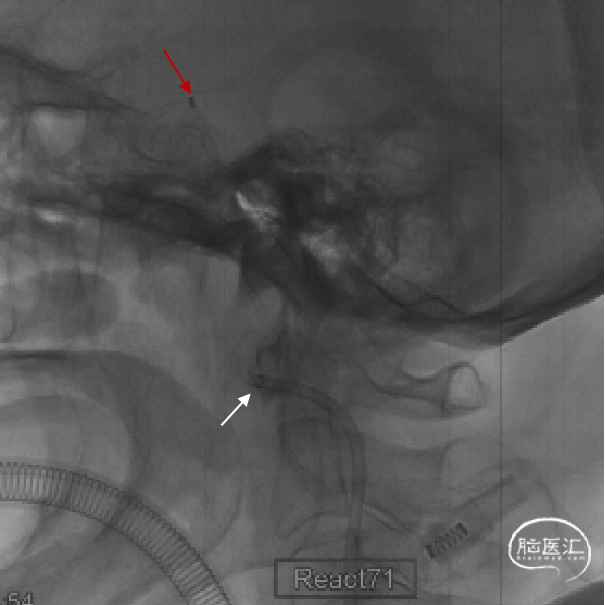

持续接触抽吸90秒后,回撤抽吸导管;抽吸导管进入长鞘之前,开启长鞘负压抽吸;发现血栓卡在长鞘头端、抽吸导管撤出长鞘后发现长鞘内无回血(白色短箭头)。20ml注射器连接长鞘、持续负压抽吸下撤出长鞘;长鞘在进入8F穿刺鞘前,开启穿刺鞘负压抽吸(白色长箭头)。最终成功将血栓从长鞘内抽吸出。

1. 本病例治疗过程相对简单:房颤栓子脱落堵塞右侧颈内动脉末端(“T”型),采用大口径抽吸导管强化抽吸取栓技术(E-ADAPT),一次取栓完全再通血管。

3. 此外,抽吸导管接触血栓核心是抽吸取栓的关键。术前对于血栓位置的判断决定了术中抽吸导管的位置。颈内动脉末端闭塞发生近端假性闭塞的比例高达50%;尤其是累及眼动脉的颈内动脉末端闭塞,该类病例DSA可见颈内动脉颅外段全程显影受限,易被误判为颈内动脉夹层或颈内动脉起始部重度狭窄。房颤、瓣膜病等来源的栓子,往往血栓负荷大、质韧;当栓子堵塞抽吸导管或导引导管时,需要强化抽吸(E-ADAPT),保证血栓完整取出、减少血栓脱落,提高手术效率。